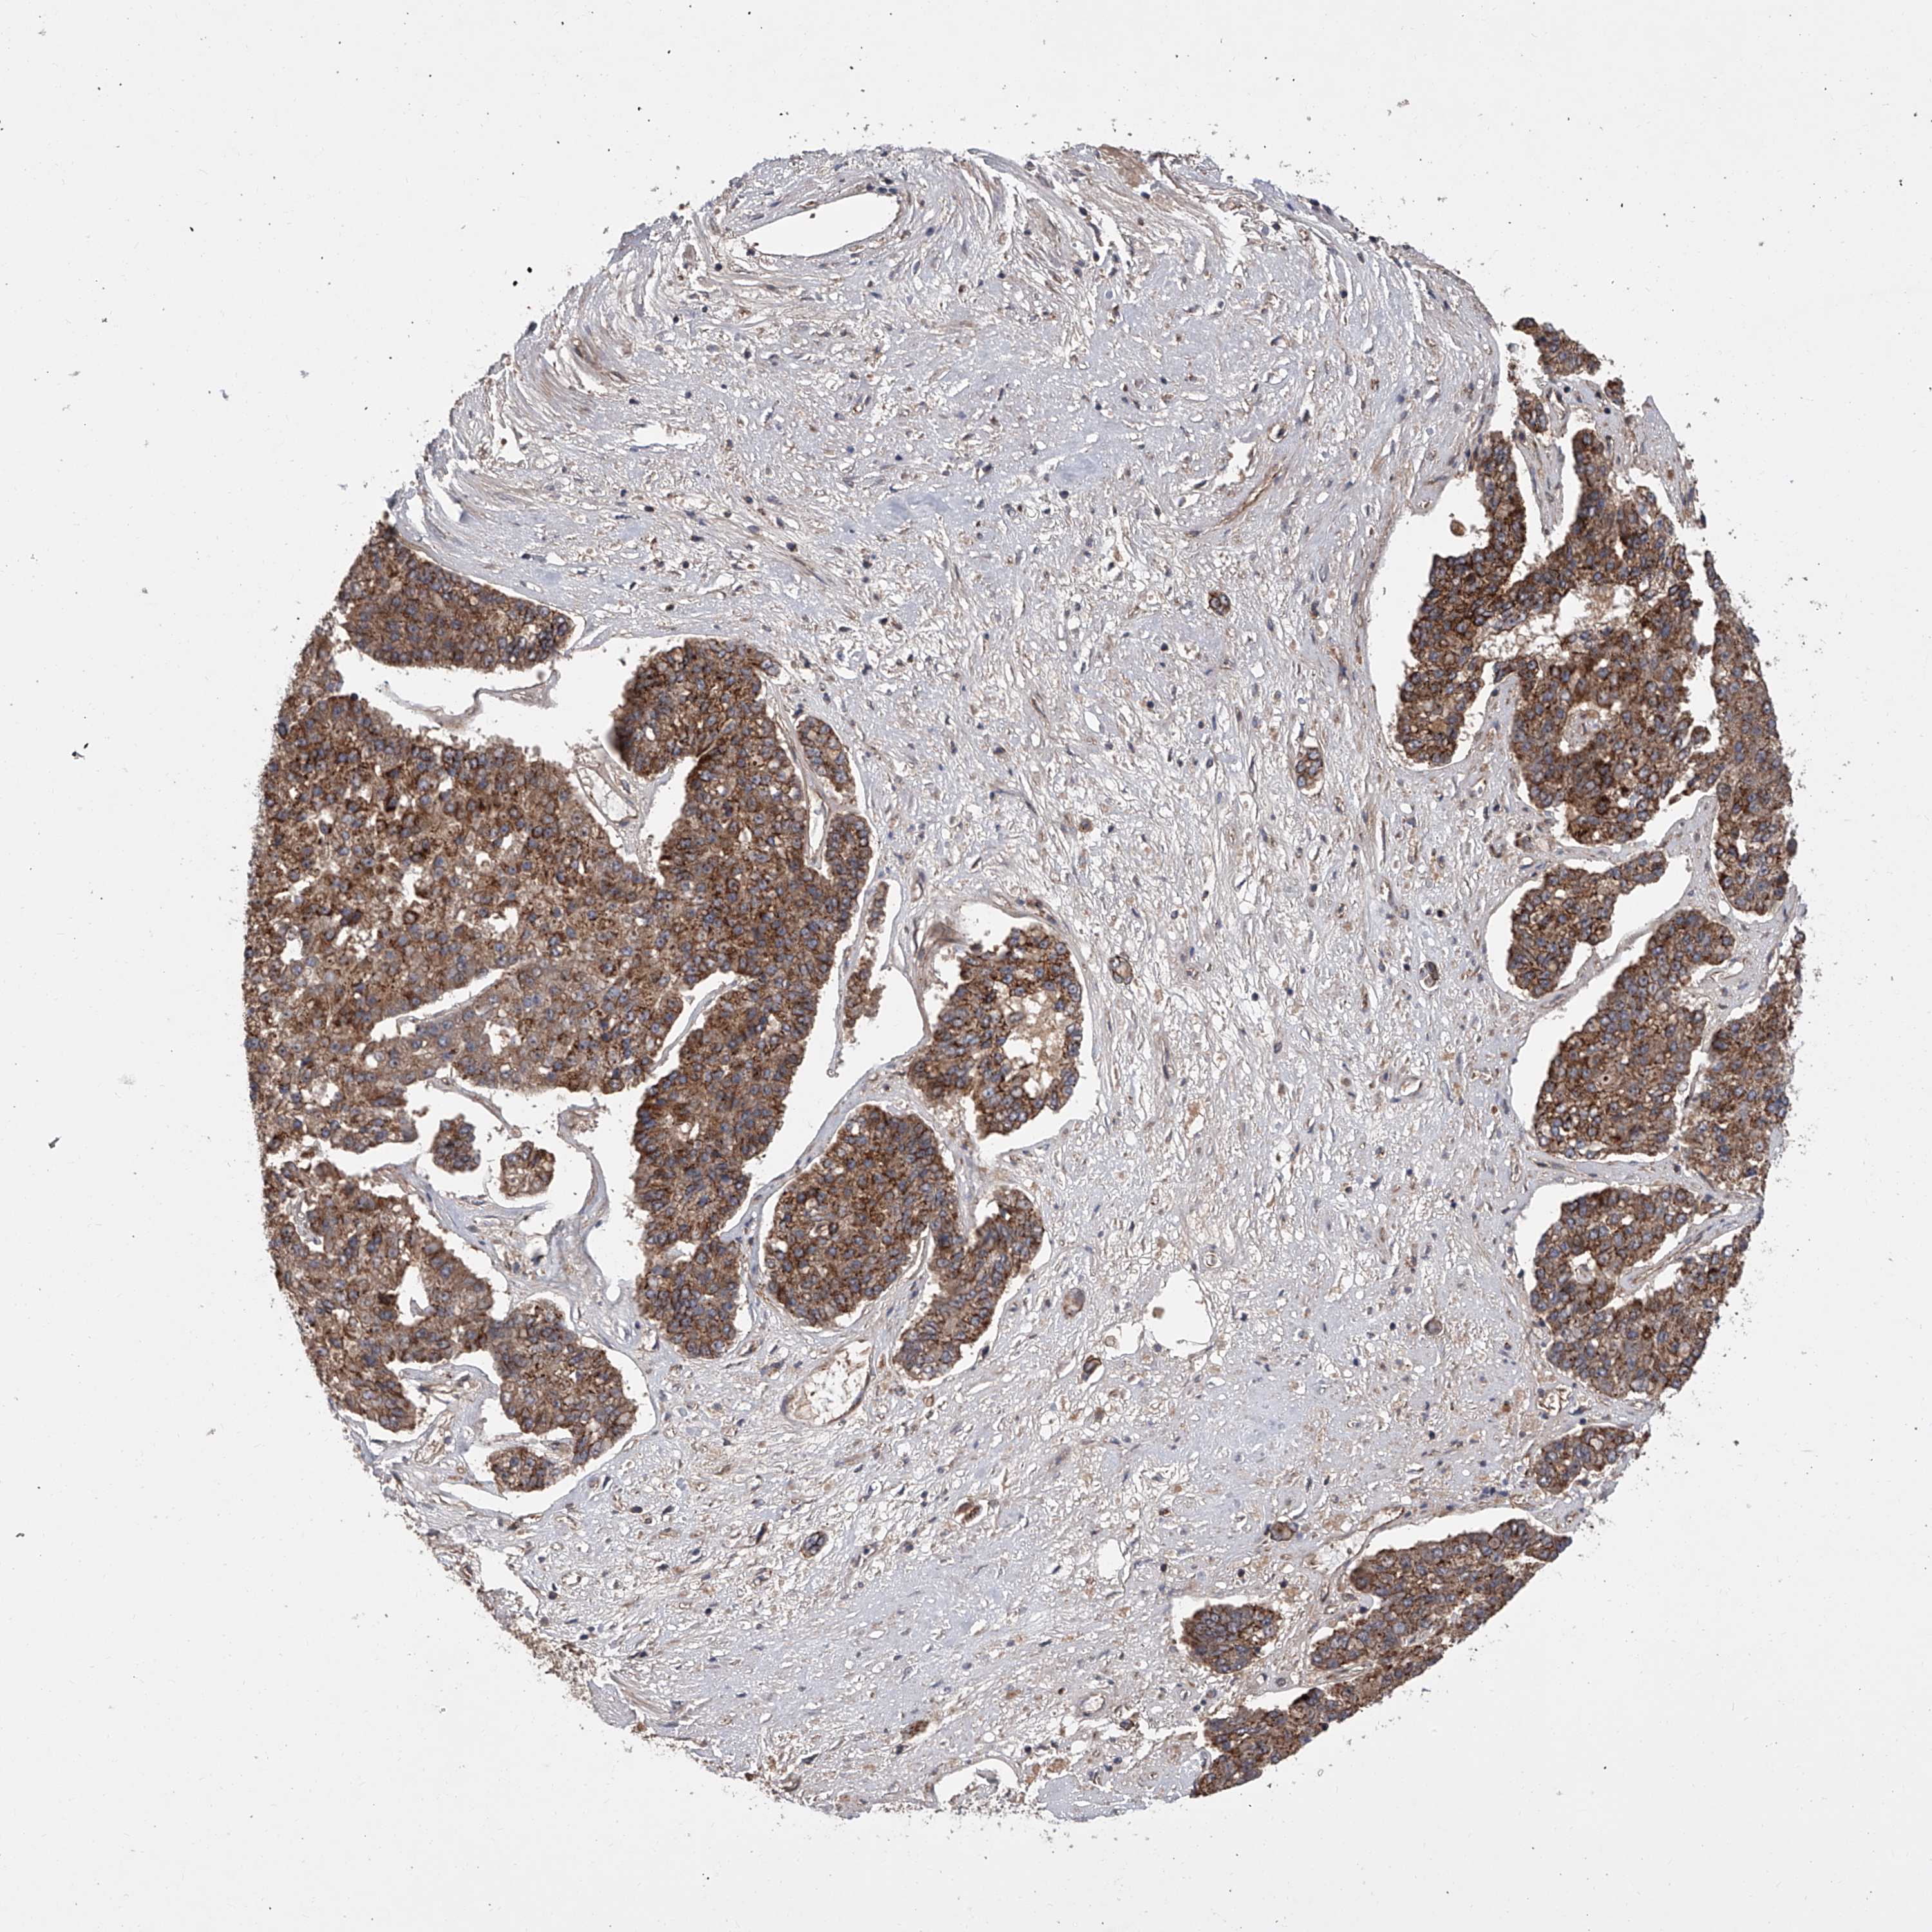

PANCREATIC CANCER - Protein expressioni

A mouse-over function shows sample information and annotation data. Click on an image to view it in a full screen mode. Samples can be filtered based on level of antibody staining by selecting one or several of the following categories: high, medium, low and not detected. The assay and annotation is described here.

Note that samples used for immunohistochemistry by the Human Protein Atlas do not correspond to samples in the TCGA dataset.

Antibody stainingi

Antibody staining in the annotated cell types in the current human tissue is reported as not detected, low, medium, or high, based on conventional immunohistochemistry profiling in selected tissues. This score is based on the combination of the staining intensity and fraction of stained cells.

Each image is clickable and will lead to virtual microscopy that enables deeper exploration of all samples and also displays staining intensity scores, fraction scores and subcellular localization as well as patient and tissue information for each sample.

Antibody HPA029286

Antibody HPA029289

Adenocarcinoma, NOS